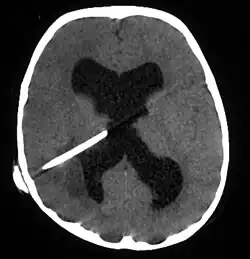

| Brain abscess in a person with a CSF shunt. The abscess is the darker gray region in the lower left of the image (corresponding to the right parietal lobe). The lateral ventricles are visible in black in the center of the brain, adjacent to the abscess.[1] | |